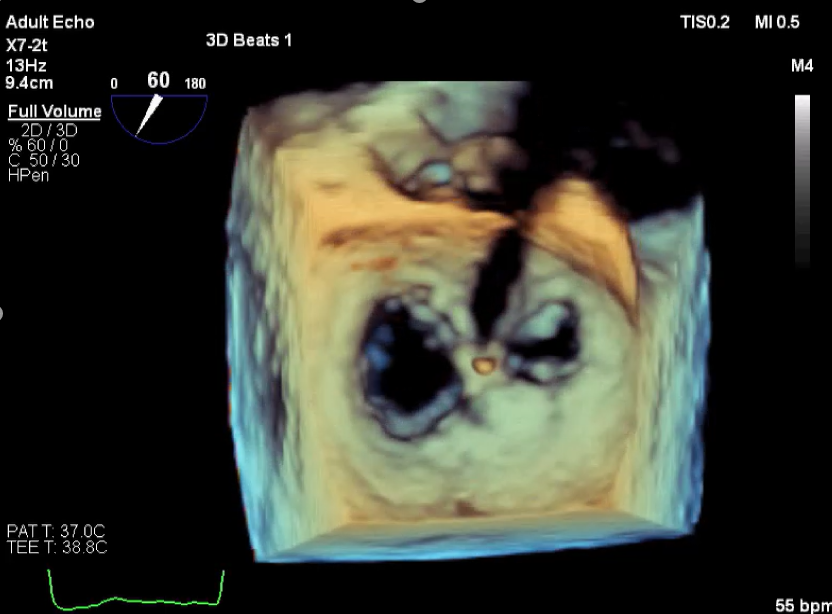

3D视图打开夹子

3D视图下观察二尖瓣双孔形态